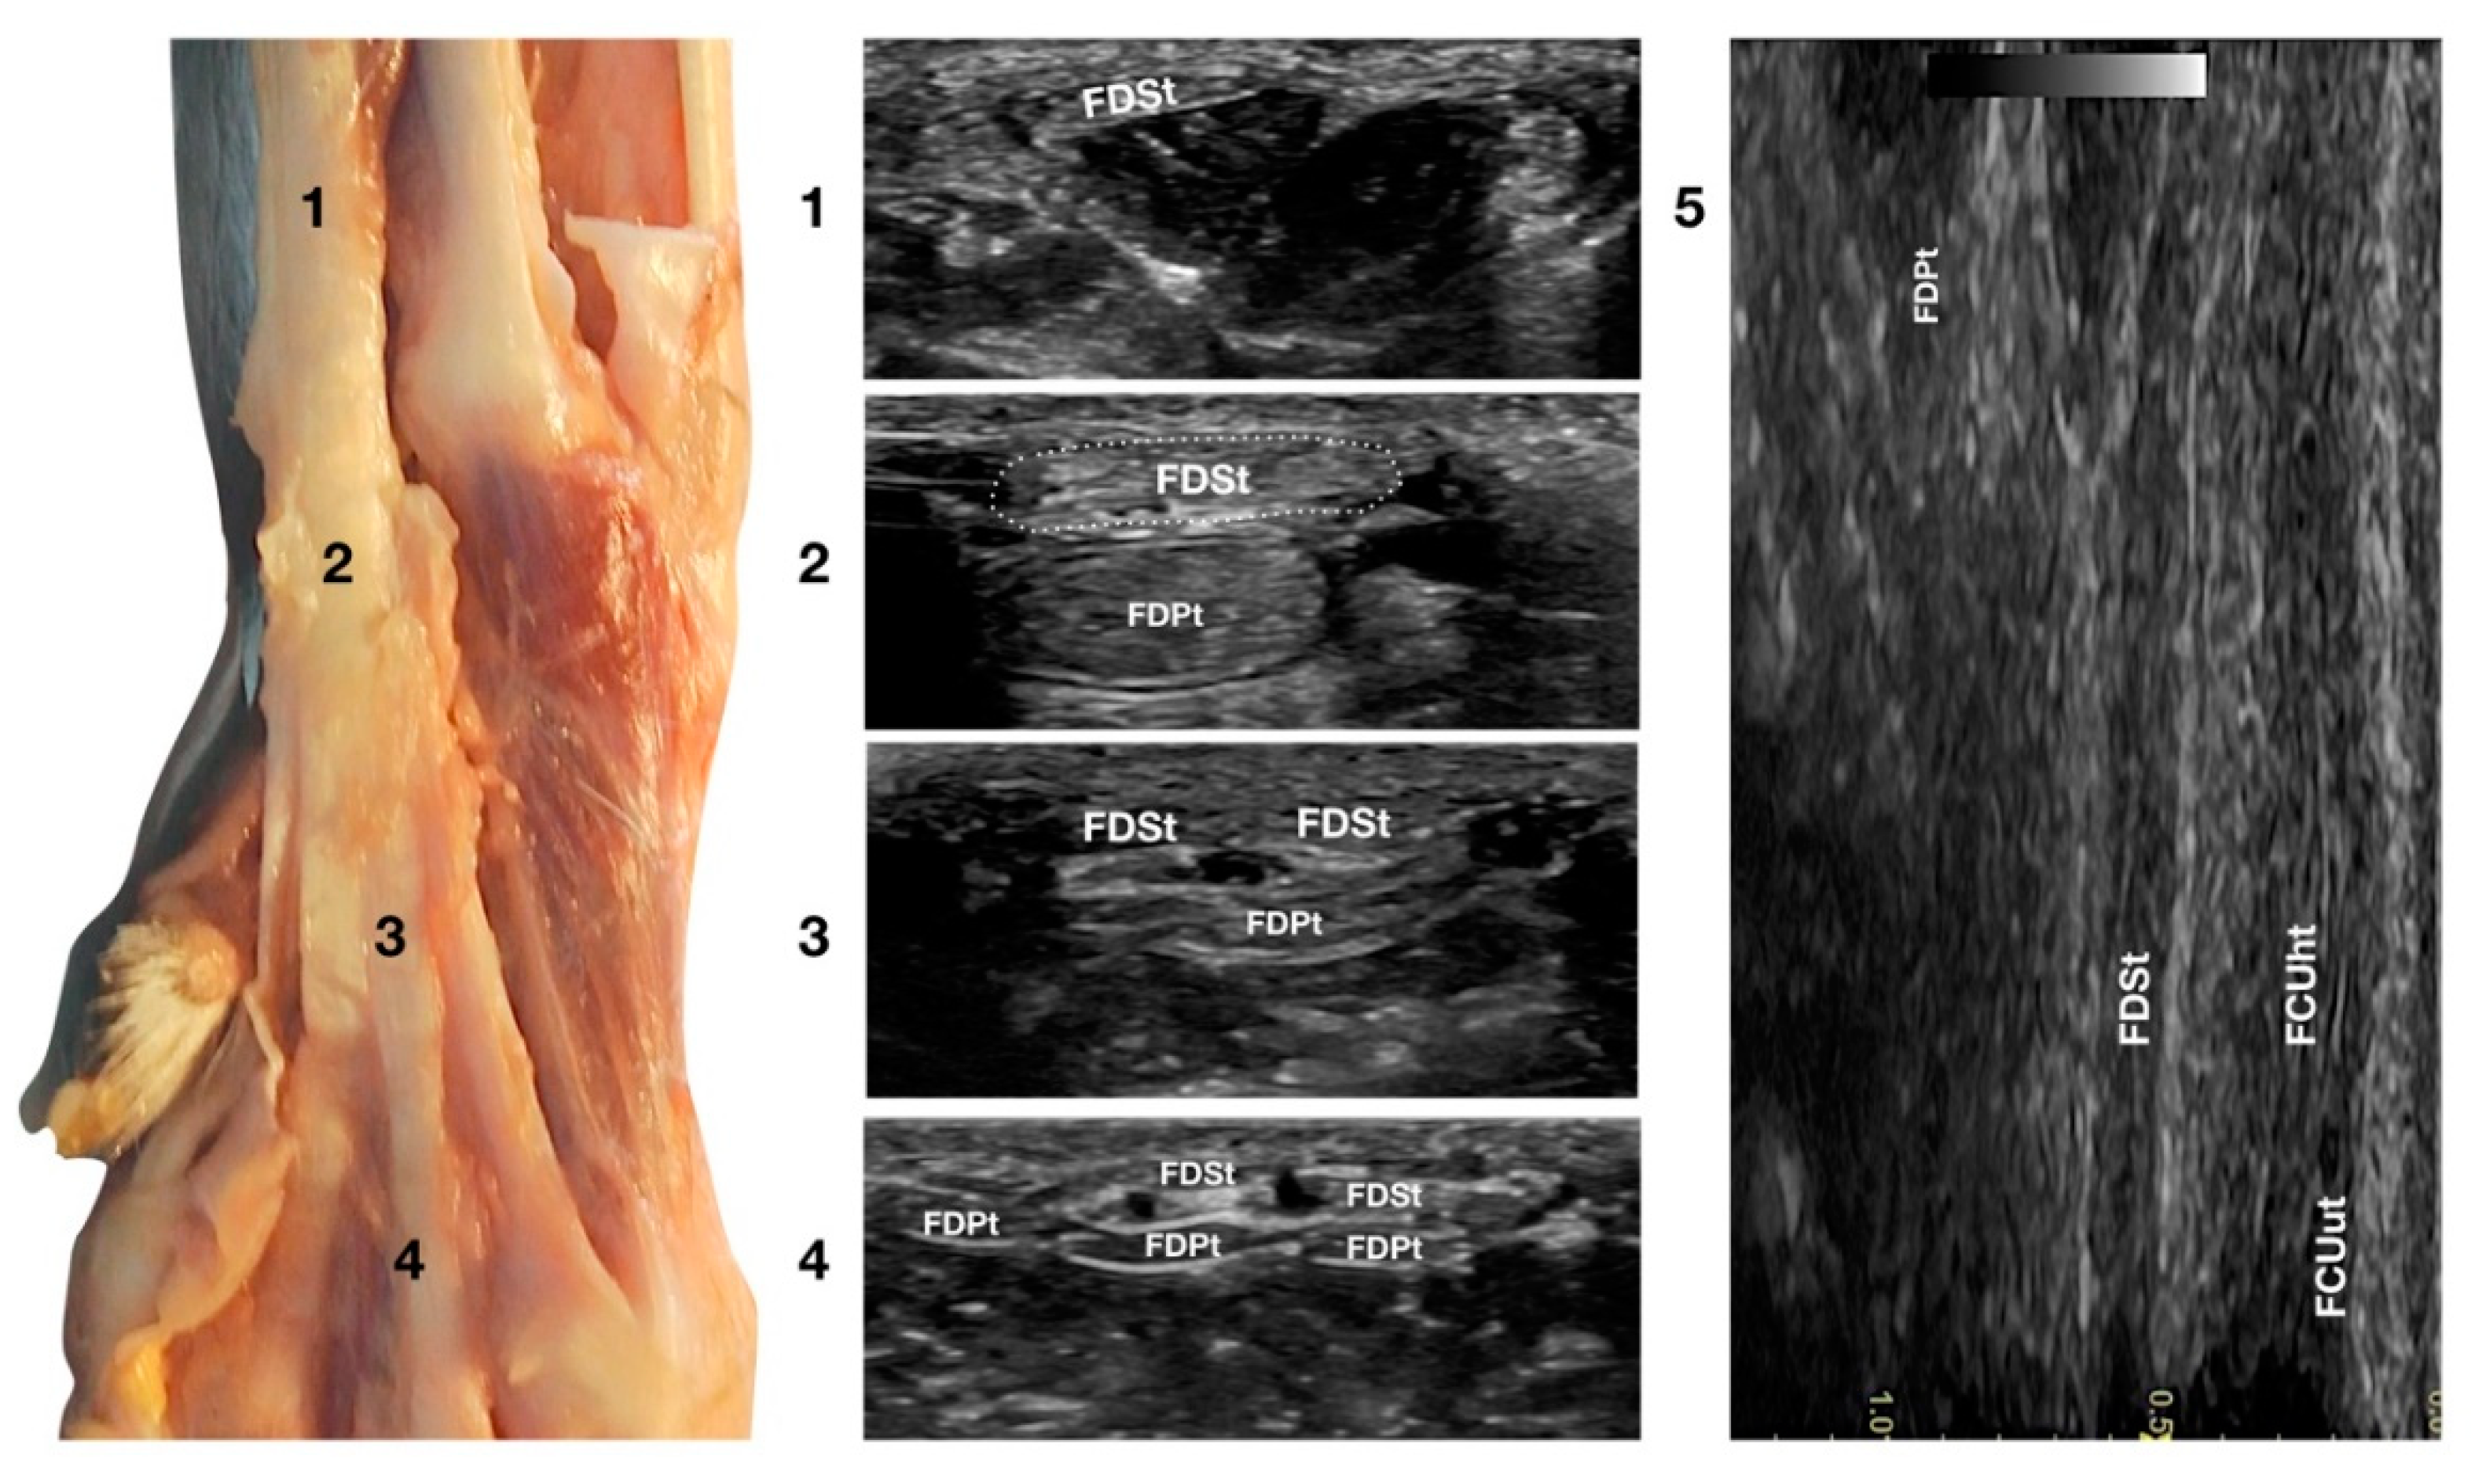

3.3.2. Flexor Digitorum Superficialis Tendon Ultrasonographic Anatomy (FDSt)

Just medial to the accessory bone, so close that in a longitudinal scan plane, a minimal medial angulation of the probe gave the impression of some degree of continuity with the FCUt; the Flexor Digitorum Superficialis tendon (FDSt) was seen parallel to the FCUt but extending distally to the accessory carpal bone (Figure 1c). On transverse images, moving the probe slightly medially to the accessory bone, the FDSt was seen as a large, echoic, elliptical structure, approximately twice as wide as thick. The Flexor Retinaculum was a thick connective layer that created a nearly uniform echoic ring surrounding the tendon and separating its deeper margin from the Flexor Digitorum Profundus tendon (FDPt) beneath (Figure 7).

Figure 7.

Palmar carpal face centred on the Flexor Digitorum Superficialis tendon. At the ulnar notch level (2), the FDSt is a broad and flattened elliptical structure surrounded by echoic ill-defined tissue (the Retinaculum). It is just superficial to the larger Flexor Digitorum Profundus tendon. Proximally, the tendon is very superficial and flat at the tenomuscular junction (1). Distally, in the proximal third of the metacarpus (3), the tendon starts to divide into four structures that diverge and follow the more profound and larger parts of the FDPt (4). On the longitudinal scan (5), obtained by putting the probe in the hollow medially to the accessory carpal bone and angling the probe slightly laterally, the fine fibrillar pattern of the FDSt is seen parallel and separated from the more lateral and superficial FCUt by fat and the Retinaculum. The deeper FDPt is barely visible since it is not perfectly parallel to the other two tendons. The FDPt starts deeper and runs obliquely to become relatively superficial at the accessory bone passage where it pairs with the FDSt until their termination.

Progressing proximally, the tendon quickly became thinner and broader, assumed a superficial position, and was separated from the FDPt by several muscle bellies. Just distal to the accessory bone, the tendon thickened and paired with the deeper FDPt. In the proximal third of the metacarpus, the FDSt flattened, becoming progressively thinner and remaining superficial to the thicker FDPt. At this level, they split into four parts that diverged from the second to the fifth metacarpophalangeal joint. At this level, the paw partially interferes with the visibility of such small structures. By elevating the foot and using the palmar aspect of the digit with a golf stick probe, it was possible to have an acoustic window distal to the paw pad. This small window often made it possible to recognise it in a transverse scan, a small elliptical structure corresponding to the fusion of the FDS and FDP tendons. A rich fibrillar tendinous pattern was noted in the longitudinal scan of the tendon. The phalangeal termination was often best visualised in the longitudinal scan plane using the palmar digital surface, and a single thin tendon, representing the combination of the FDS and the FDP tendons, was sometimes recognised and rarely followed up to the FDSt insertion at the palmar surface of the base of the middle phalanx. Flexing and extending the digits and the carpus, and stressing the carpus and the digits mediolaterally enhanced the range of motion and the degree of tendon compliance, and tested the Extensor Retinaculum function.

3.3.3. Flexor Digitorum Profundus Tendon Ultrasonographic Anatomy (FDPt)

In the hollow between the protruding portion of the accessory carpal bone and the caudal margin of the radial ulnar notch, in a transverse scan plane, the more superficial and elliptical FDSt and the deeper, larger and rounder Flexor Digitorum Profundus tendon (FDPt) were easily seen as paired structures (Figure 1d). Using an adequate amount of gel helped to align the probe with an area having an uneven surface. The thick tendon was grooved on the palmar surface of the carpus that was converted into the carpal canal by the Flexor Retinaculum surrounding the FDS and the FDP tendons (Figure 8).

Figure 8.

Palmaromedial carpal face centered on the Flexor Digitorum Profundus tendon. The FDSt were displaced to show the FDPt beneath. At the ulnar notch level (2), the FDPt is a wide, thick, oval structure, surrounded by ill-defined echoic tissue (the Retinaculum). It is just a little deeper but is in close contact with the thinner Flexor Digitorum Superficialis tendon. Proximally, at the tenomuscular junction (1), the tendon is located in a deep position. It runs obliquely distally, becoming progressively more superficial until the level of the radial notch where it pairs with the FDSt (2). At the level of the proximal third of the metacarpus, the tendon becomes thinner and wider (3) until it starts to divide into four parts that diverge and follow the superficial and thinner parts of the FDSt (4). The thin tendons of the FDS and of the FDP are outlined by the small branches of the digital veins (dv). The thick interosseous muscles (IO) separate the tendons from the third (P3), fourth (P4), and fifth (P5) metacarpal bones. On the longitudinal scan (5) obtained by putting the probe in the hollow area medial to the accessory bone and angling the probe slightly medially, the fine fibrillar pattern of the FDPt is seen, converging toward the FDSt. The more superficial FCUt and the accessory bone (AC) are barely visible.

Proximally, the FDPt ran obliquely and had a deep position, relatively closed to the caudal margin of the radius and ulna. The obliquity of the tendon with respect to the surface of the skin created the false impression of a relatively hypoechoic tendon, due to an anisotropy artefact. The tendon became parallel to the skin at the level of the accessory carpal bone and, at this level, it appeared as a large, oval, echoic structure with a rich fibrillar pattern. On the proximal portion of the metacarpus, the FDP tendon divided into four branches from digits II to V and ran distally, covered by the corresponding branches of the FDS tendon. The technique for checking the distal aspect of the tendon was the same as that previously reported for the FDSt. While the FDSt inserted into the palmar surface at the base of the middle phalanx, the FDPt inserted into the tuberosities of the distal phalanges of digits II to V. This part was only visible if accurate preparation of the palmar pad of the digits was carried out. Abundant gel was applied to an elevated pad for at least five minutes before the scanning. In some patients, the dryness and thickness of the palmar pad prevented imaging of this region. On the longitudinal scan, a dense fibrillar pattern was recognised in the proximal portion of the tendon while, in the most distal and thinner portion, the tendon appeared relatively hypoechoic and uniform, especially when the tendon thickness was less than 1 mm. The oblique path of the tendon emerging from a deep position to be parallel to the FDSt was better assessed on the longitudinal plane. The flexion and extension of the carpus and the digits, together with the mediolateral stressed poses, were used to assess adhesions, range of motion, and subluxations of the tendon.